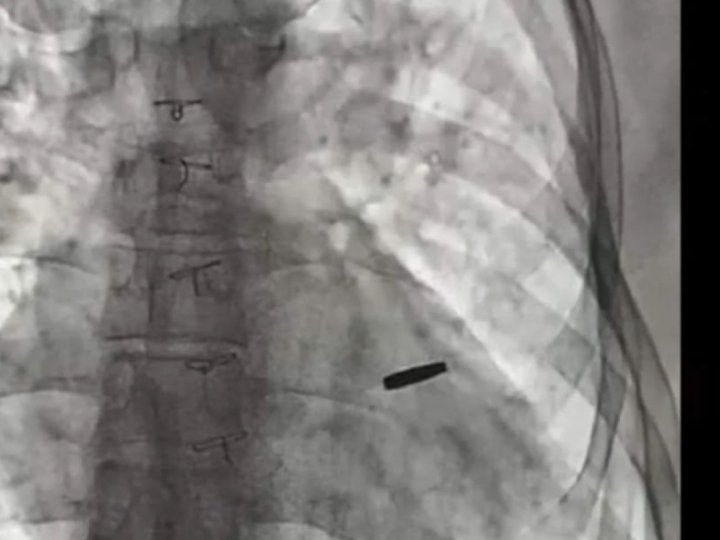

З серця звільненого з російського полону українського військового дістали кулю, з якою він прожив три роки.

Поранений військовий захищав «Азовсталь» і потрапив до полону під час атаки на Маріуполь. Три роки він був у неволі, а два місяці тому його обміняли.

«Три роки він був з цієї кулею, прожив. На щастя, вона нічого не пошкодила, зараз ми її видалили, пощастило хлопцю», — наголосив Тодуров.